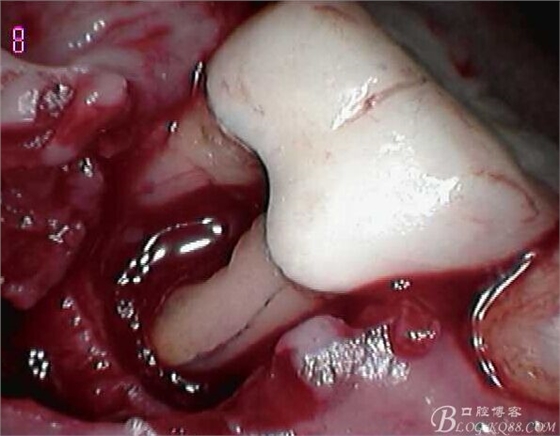

頰側(cè)翻瓣見,頰側(cè)骨壁完全缺損,同時見近遠中根都有縱向裂紋,

無法保留,

建議拔除C6,延期種植,

因C5遠中骨壁完全喪失,

調(diào)合觀察C5,